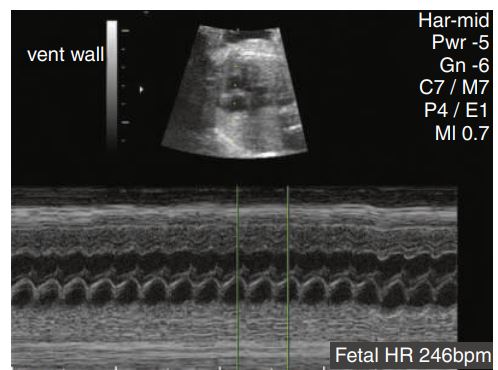

Tachycardia was identified in this patient with a heart rate of 246 beats/min.

___________ caused by cardiac insufficiency is one of the most common causes. Cardiac insufficiency can result from cardiac anomalies or arrhythmias .

Nonimmune hydrops